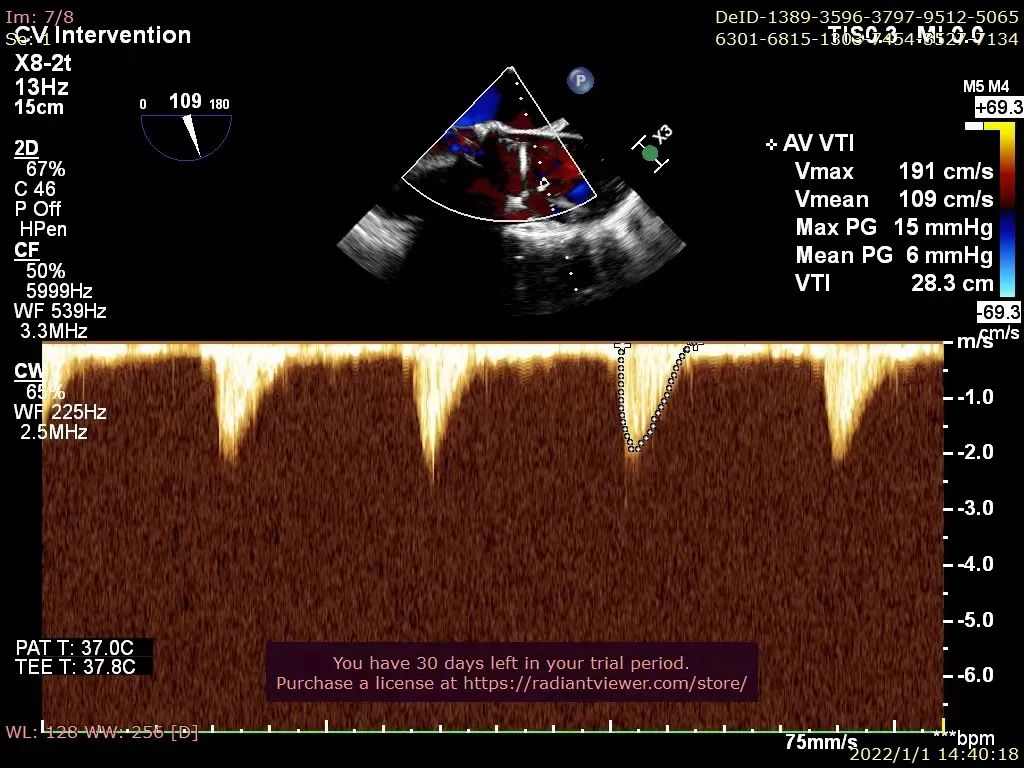

术后超声评估:

入院超声评估LVEF值仅为39%,TNT 197ng/ml,NT-proBNP 13231pg/L,CREA 67 μmlo/L,BP 86/42 mmHg,STS score 7.325%。超声诊断为瓣膜性心脏病主动脉瓣狭窄(重度),主动脉瓣反流(中度),二尖瓣关闭不全(中度)。左房扩大;左室壁增厚;左室整体运动幅度普遍降低。左室收缩功能减低。微量心包积液。此次患者急诊入院即发生急性左心衰,予IABP维持下生命体征尚平稳,经结构性心脏病团队评估患者无法耐受传统外科开胸手术,遂拟行TAVR手术治疗。